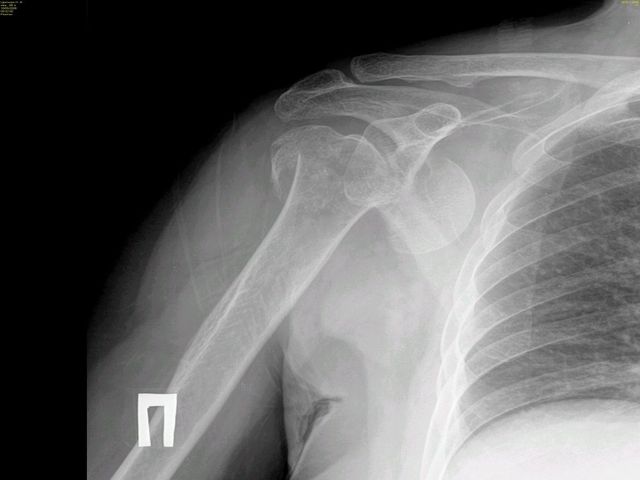

Re: несвежий переломо-вывих плеча

совершенно согласен - лучший выход эндопротезирование. Открытое вправление переломовывиха ( анатомическая шейка плеча) через 3 недели после травмы у 68летней бабушки не 99,9% обречено на неудачу.